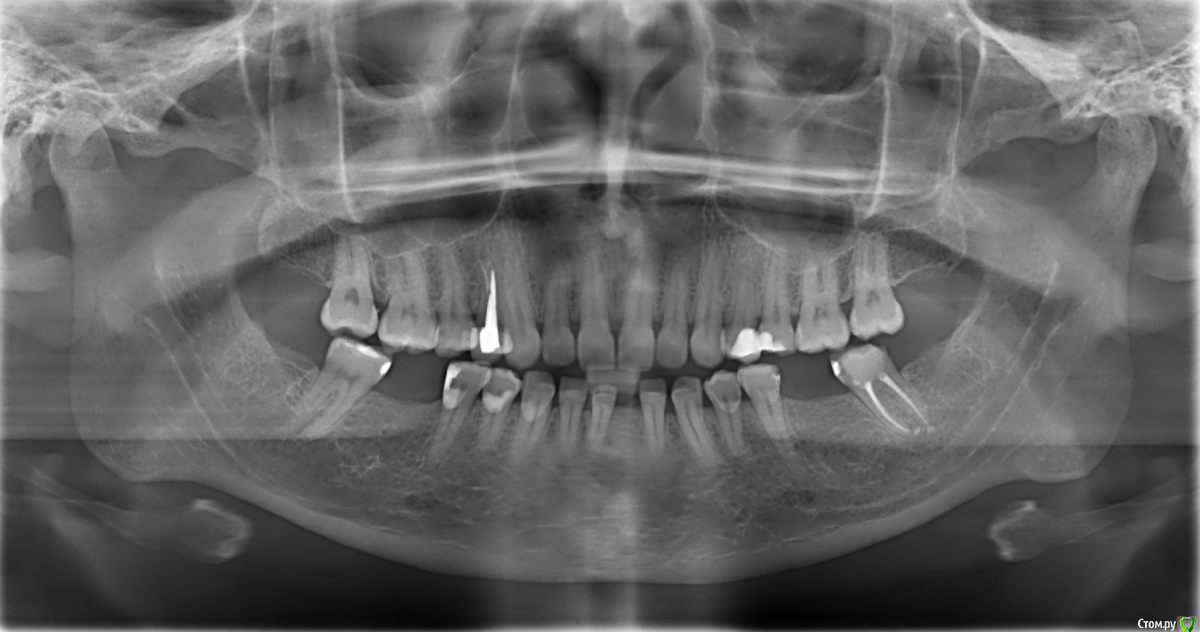

svetanik8 Опубликовано 25 мая, 2017 Поделиться Опубликовано 25 мая, 2017 Уважаемые врачи, прошу совета, чтобы определиться с тем, что делать.Году на 28м узнала, что у меня неправильный прикус (прямой), с детства отсутствует нижний передний зуб (детская травма, на тот момент врачи сказали, что зубы сойдутся, все будет ок, не сошлись, но мало кто видит, что его нет, улыбка как бы не такая низкая, чтобы открывать нижний ряд зубов).Лет в 25 удалили первую 6ку в нижнем ряду, спустя пару лет вторую симметрично, итого имею три проблемы, которые нужно решить (имплантация либо мост). Посетила пару врачей, один ортодонт предложил установить брекеты только на несколько нижних зубов с тем, чтобы сделать место для импланта на месте отсутствующего переднего, так как прикус меня 30 лет до этого не беспокоил, мне зубы кажутся ровными. Врач имплантолог в этой же клинике предложил по всем трем отсутствующим зубам сделать какое-то расщепление с подсадкой, при котором сразу же ставится имплант, причем обе шестерки предложил объединить в одну операцию, чтобы сэкономить на какой-то мембране.Второй врач сказал делать подсадку ткани по всем трем, по брекетам ничего не прокомментировал, отдельно нужно общаться с ортодонтом.И еще один врач тоже сказал, что нужно делать подсадку костной ткани, что расщепление ему не очень нравится в принципе, что может отломаться кость и тп. Подсадка костной ткани очень недешевая процедура (или я ходила в такие клиники дорогие, не знаю). Вопрос, стоит ли в моем случае делать импланты (по каждому зубу) или где-то лучше мост (например, семерка слева под коронку уже, там ползуба нет).Прилагаю снимки ОПТГ и КТ (скриншоты, если нужны другие ракурсы скажите, пока не разобралась как их делать).Отдельный вопрос по брекетам, не знаю выносить ли в отдельнуютему, проблема комплексная. На всякий случай еще фото обычные зубов.Спасибо заранее. Ссылка на комментарий

колесников Опубликовано 26 мая, 2017 Поделиться Опубликовано 26 мая, 2017 тактика зависит от предпочтений и умений доктора. все вышеизложенные методы могут быть применимы в вашем случае. с костной пластикой или без-это детали.Я бы не проводил костных пластик ,но это мое видение.Вобласти 31 необходима предварительная ортодонитеская подготовка Ссылка на комментарий